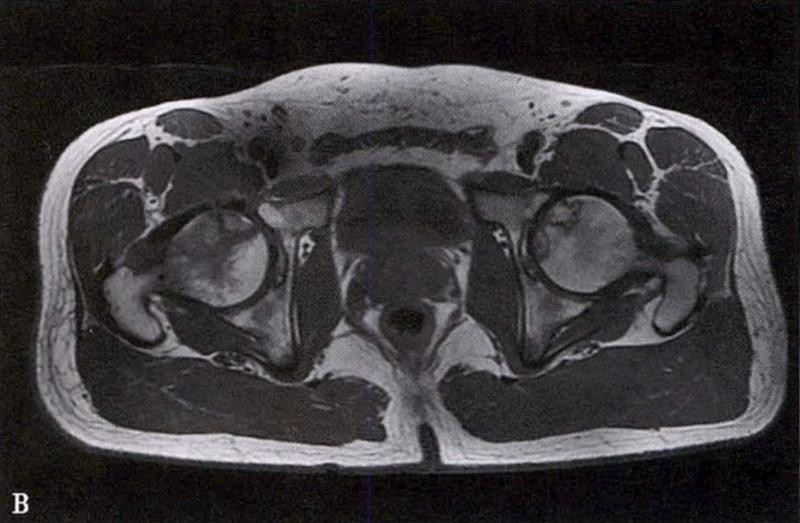

(2)MRI检查

MRI检查是早期诊断股骨头坏死最具特异性、灵敏度的检查方法。当怀疑有股骨头坏死,而X线片无明显异常时,应行MRI检查。诊断时可根据髋关节X线、MRI显示的坏死面积和塌陷程度进行ARCO分期。

冠状面及横断面MRI图像

MRI示双侧股骨头坏死,冠状面显示右侧股骨头坏死(图A、C),横断面显示双侧股骨头坏死(图B、D);T1加权像(图A、B)显示硬化带为低信号,T2加权像(图C、D)显示右侧骨坏死硬化带外围高信号的骨髓水肿,左侧无骨髓水肿。